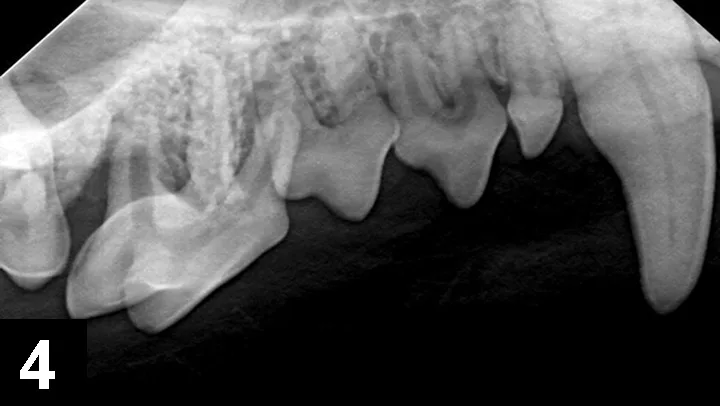

A parulis is an opening of an intraoral sinus tract in the oral mucosa; hidden periodontal disease is often indicated if the parulis is within the gingiva (Figures 3 and 4). Periodontal disease is caused by a subgingival biofilm (an adherent bacterial community living in an exopolysaccharide matrix that protects the bacteria and allows cooperation of the microorganisms) that results in loss of attachment of the periodontium (ie, gingiva, alveolar bone, periodontal ligament, cementum), regardless of the amount of plaque or calculus on the supragingival crown. Periodontal disease is predominately a subgingival disease, so general anesthesia and intraoral radiographs are required. Extraction is often necessary for periodontal disease associated with a parulis. If the parulis is within the oral mucosa, it is likely caused by endodontic disease, and root canal treatment may be an option. A parulis at the mucogingival junction might be caused by either periodontal or endodontic disease.

Combined vertical and horizontal bone loss of the distal and buccal roots of tooth 108 from the patient in Figure 3, resulting in almost complete bone loss. The tooth has a wide pulp canal compared with other teeth, indicating the pulp in this tooth died a long time ago (combined periodontal–endodontic disease). Surgical extraction is the only option in this case. The pulp chambers in tooth 106 wider than the other teeth, indicating that the pulp in this tooth is also necrotic and requires extraction.